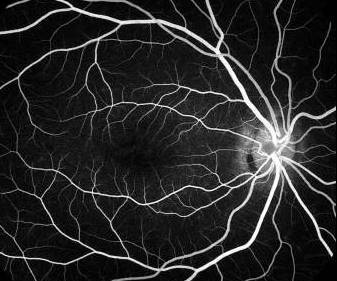

Fluorescein angiography:

Case seven

What does this fluorescein angiography show?

This fluorescein angiography is taken at the venous

phase of the right fundus. The choroidal fluorescein

is absent given a picture of dark choroid.

Suggest some possible causes.

Abnormal deposition of substances at the layers of

the RPE that blocks the transmission of the choroidal

fluorescein. This can occur with Stargardt's

disease or argyrosis.

Choroidal ischaemia.

This patient has atypical Stargardt's disease in that

the typical pisciform flecks are absent (the flecks

are usually hyperfluorescence)